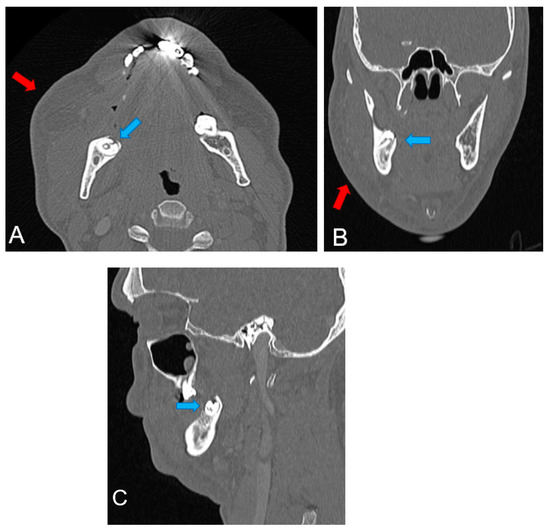

2. Detailed Case Description